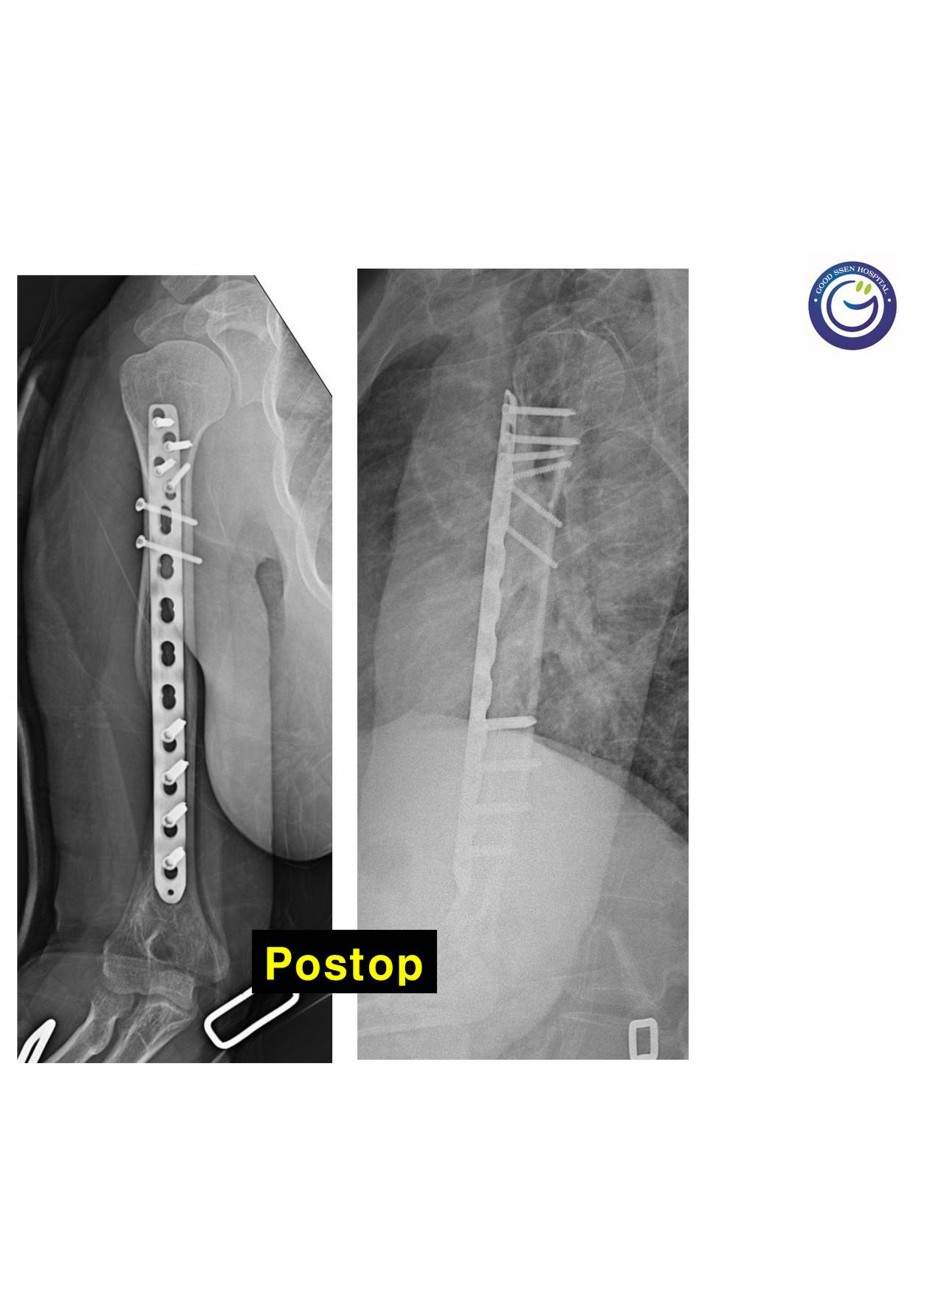

관절을 침범하는 심한 분쇄골절

절개없이 고정하는 최소침습적 고정방법 (MIPO)